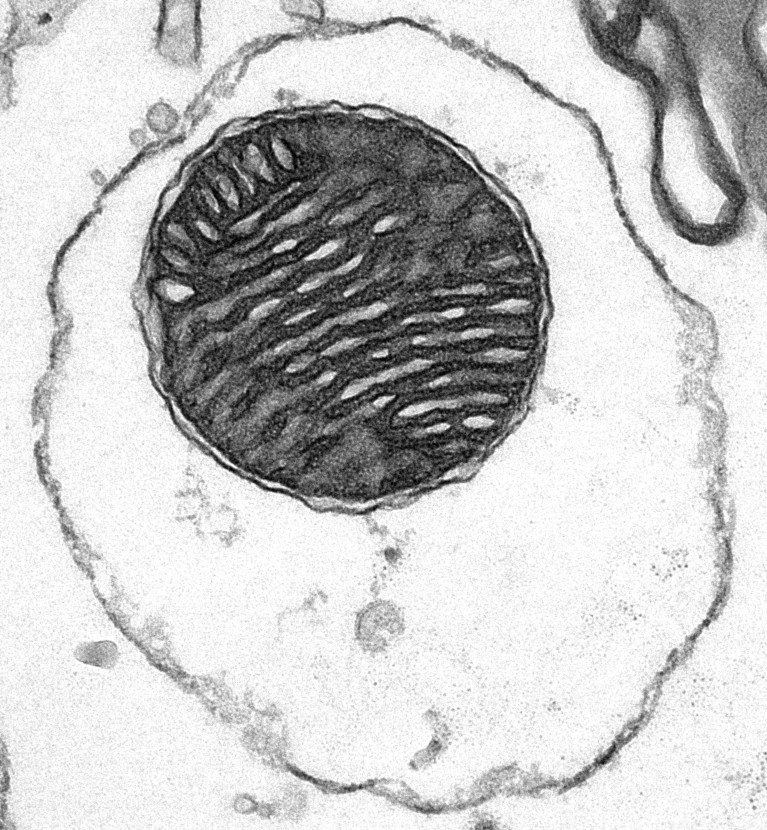

A ‘capsule’ of mitochondria (central dark circle) is enclosed by a red blood cell’s membrane (outer dark oval).Credit: S. Du et al./Cell

The “shell” preserves the mitochondrion’s electrical gradient, says co-author Qi Long, a biologist at Guangzhou Medical University in China. That allowed the organelles to slip into recipient cells undetected.

The authors of the Cell study settled on using the membranes of red blood cells because the cells lack organelles with their own membranes. Creating the mitochondrial ‘capsules’ was then as simple as mixing ruptured red blood cells and mitochondria isolated using a commercially available kit. The scientists then injected these ‘capsules’ into mice.